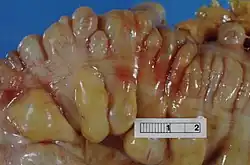

| Section of the large bowel (sigmoid colon) showing multiple pouches (diverticula). The diverticula appear on either side of the longitudinal muscle bundle (taenium), which runs horizontally across the specimen in an arc. | |